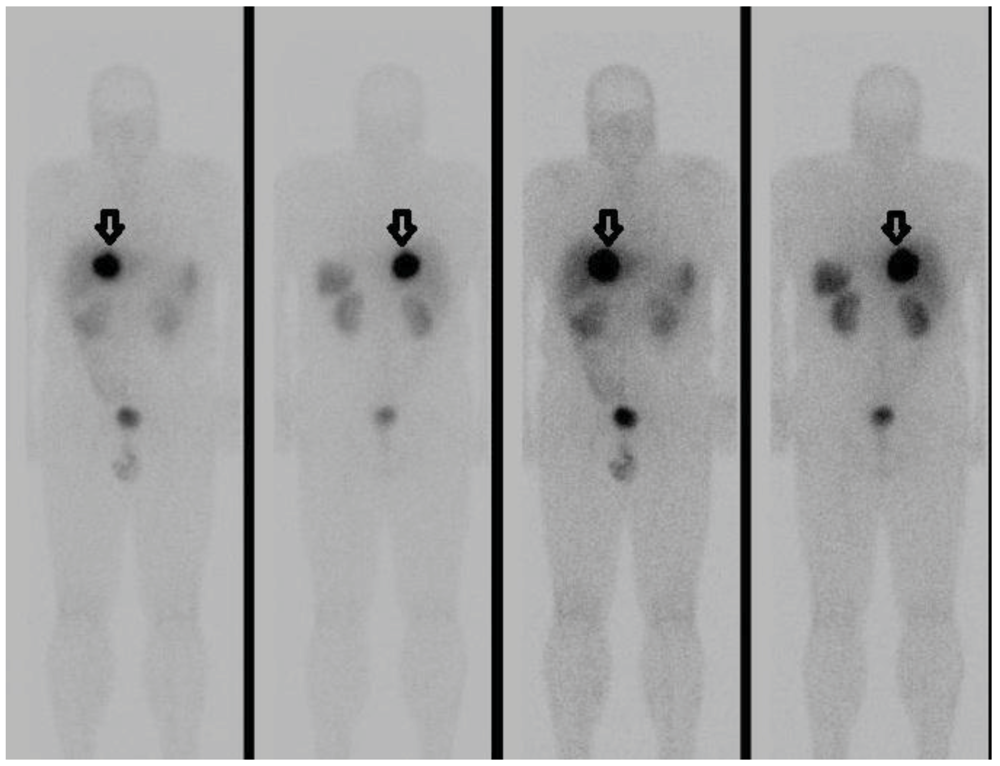

Primary Hepatic Gastrinoma Causing Zollinger-Ellison Syndrome: A Rare and Challenging Diagnosis

2. Case Report